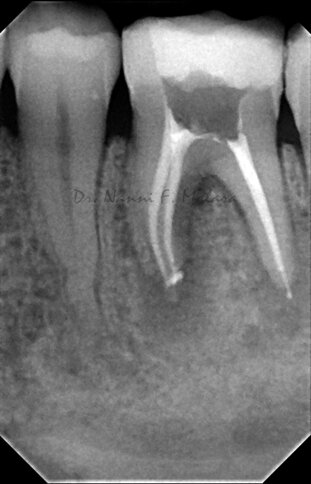

Terapia endodontica con sigillo tridimensionale dei canali radicolari